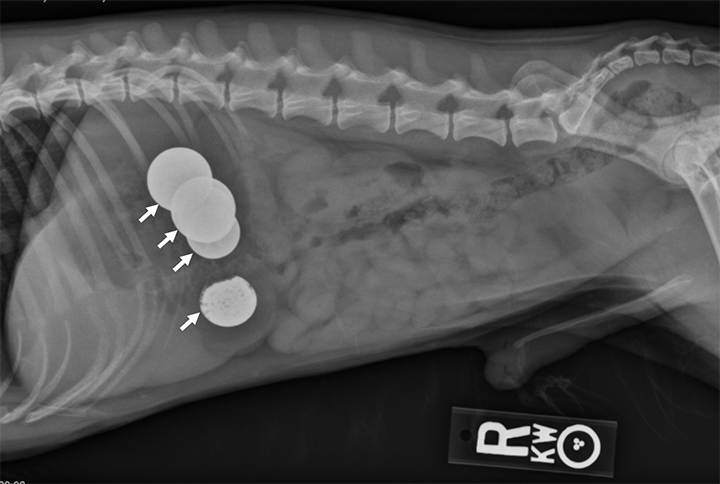

Bobs for dogs x ray top, A Visual Guide to GI Obstruction on Radiographs top

A Visual Guide to GI Obstruction on Radiographs

A Visual Guide to GI Obstruction on Radiographs

Thought you would find the radiographs of my pet rat Bob s badly sprained back right leg interesting. r Radiology top, Thought you would find the radiographs of my pet rat Bob s badly sprained back right leg interesting. r Radiology top, Newfoundland Dog Health Center top, X ray of dog lateral view with Gastric dilatation volvulus GDV or stomach twists Double bubble pattern indicates stomach torsion has occurred Veterinary medicine and Veterinary anatomy Concept. Stock... top, A Visual Guide to GI Obstruction on Radiographs top, Newfoundland Dog Health Center top, How Nestle s leg almost got amputated Dr Phil Zeltzman s Blog top, Radiography of the Small Animal Skull Temporomandibular Joints Tympanic Bullae Today s Veterinary Practice top, Loving Paws Pet Clinic Low stress veterinarian in Savoy IL X rays top, A Visual Guide to GI Obstruction on Radiographs top, Small Animal Elbow and Antebrachium Radiography Today s Veterinary Practice top, Understanding X rays can save dollars and lives WCVM Today Western College of Veterinary Medicine University of Saskatchewan top, A Visual Guide to GI Obstruction on Radiographs top, Radiography of the Small Animal Skull Temporomandibular Joints Tympanic Bullae Today s Veterinary Practice top, You removed how much of Mimi s jaw Dr Phil Zeltzman s Blog top, Dog X rays Variety of Radiographs Taken on Dogs top, Dog X rays Variety of Radiographs Taken on Dogs top, X ray Dog Anterior Image Photo Free Trial Bigstock top, X Ray Normal Forelimb Dog Stock Photo 689852953 Shutterstock top, DOG BOWEL OBSTRUCTION X RAY Stock Photo Image of skeleton pain 30050362 top, xray of dogs chest showing heart disease Stock Photo Alamy top, Bobby Bob Bob Tamara Kenneally Photography top, BOBs Kennels top, Radiographs for Dogs Bioscint top, Dog X rays Variety of Radiographs Taken on Dogs top, Pets will eat the strangest things top, Dog X rays Variety of Radiographs Taken on Dogs top, Lateral X ray Radiograph Left Forelimb Puppy Stock Illustration 1344763586 Shutterstock top, Top 5 Tips on Radiographic Diagnosis of Obstructive Foreign Bodies top, Dog X rays Variety of Radiographs Taken on Dogs top, Right Lateral Chest X ray Radiograph Dog Stock Illustration 1337012921 Shutterstock top, Dog X rays Variety of Radiographs Taken on Dogs top, Abdominal X Rays Made Easy top, Old Chapel Veterinary Clinic Canine elbow dysplasia ED is a disease of the elbows of dogs caused by growth disturbances in the elbow joint. Elbow dysplasia is most often seen in top, Hi Ferg swallowed a piece of flat rubber ball about 1 x2.5 a week ago. She has been asymptomatic. Xrays were taken and radiologist. PetCoach top.

Thought you would find the radiographs of my pet rat Bob s badly sprained back right leg interesting. r Radiology top, Thought you would find the radiographs of my pet rat Bob s badly sprained back right leg interesting. r Radiology top, Newfoundland Dog Health Center top, X ray of dog lateral view with Gastric dilatation volvulus GDV or stomach twists Double bubble pattern indicates stomach torsion has occurred Veterinary medicine and Veterinary anatomy Concept. Stock... top, A Visual Guide to GI Obstruction on Radiographs top, Newfoundland Dog Health Center top, How Nestle s leg almost got amputated Dr Phil Zeltzman s Blog top, Radiography of the Small Animal Skull Temporomandibular Joints Tympanic Bullae Today s Veterinary Practice top, Loving Paws Pet Clinic Low stress veterinarian in Savoy IL X rays top, A Visual Guide to GI Obstruction on Radiographs top, Small Animal Elbow and Antebrachium Radiography Today s Veterinary Practice top, Understanding X rays can save dollars and lives WCVM Today Western College of Veterinary Medicine University of Saskatchewan top, A Visual Guide to GI Obstruction on Radiographs top, Radiography of the Small Animal Skull Temporomandibular Joints Tympanic Bullae Today s Veterinary Practice top, You removed how much of Mimi s jaw Dr Phil Zeltzman s Blog top, Dog X rays Variety of Radiographs Taken on Dogs top, Dog X rays Variety of Radiographs Taken on Dogs top, X ray Dog Anterior Image Photo Free Trial Bigstock top, X Ray Normal Forelimb Dog Stock Photo 689852953 Shutterstock top, DOG BOWEL OBSTRUCTION X RAY Stock Photo Image of skeleton pain 30050362 top, xray of dogs chest showing heart disease Stock Photo Alamy top, Bobby Bob Bob Tamara Kenneally Photography top, BOBs Kennels top, Radiographs for Dogs Bioscint top, Dog X rays Variety of Radiographs Taken on Dogs top, Pets will eat the strangest things top, Dog X rays Variety of Radiographs Taken on Dogs top, Lateral X ray Radiograph Left Forelimb Puppy Stock Illustration 1344763586 Shutterstock top, Top 5 Tips on Radiographic Diagnosis of Obstructive Foreign Bodies top, Dog X rays Variety of Radiographs Taken on Dogs top, Right Lateral Chest X ray Radiograph Dog Stock Illustration 1337012921 Shutterstock top, Dog X rays Variety of Radiographs Taken on Dogs top, Abdominal X Rays Made Easy top, Old Chapel Veterinary Clinic Canine elbow dysplasia ED is a disease of the elbows of dogs caused by growth disturbances in the elbow joint. Elbow dysplasia is most often seen in top, Hi Ferg swallowed a piece of flat rubber ball about 1 x2.5 a week ago. She has been asymptomatic. Xrays were taken and radiologist. PetCoach top.